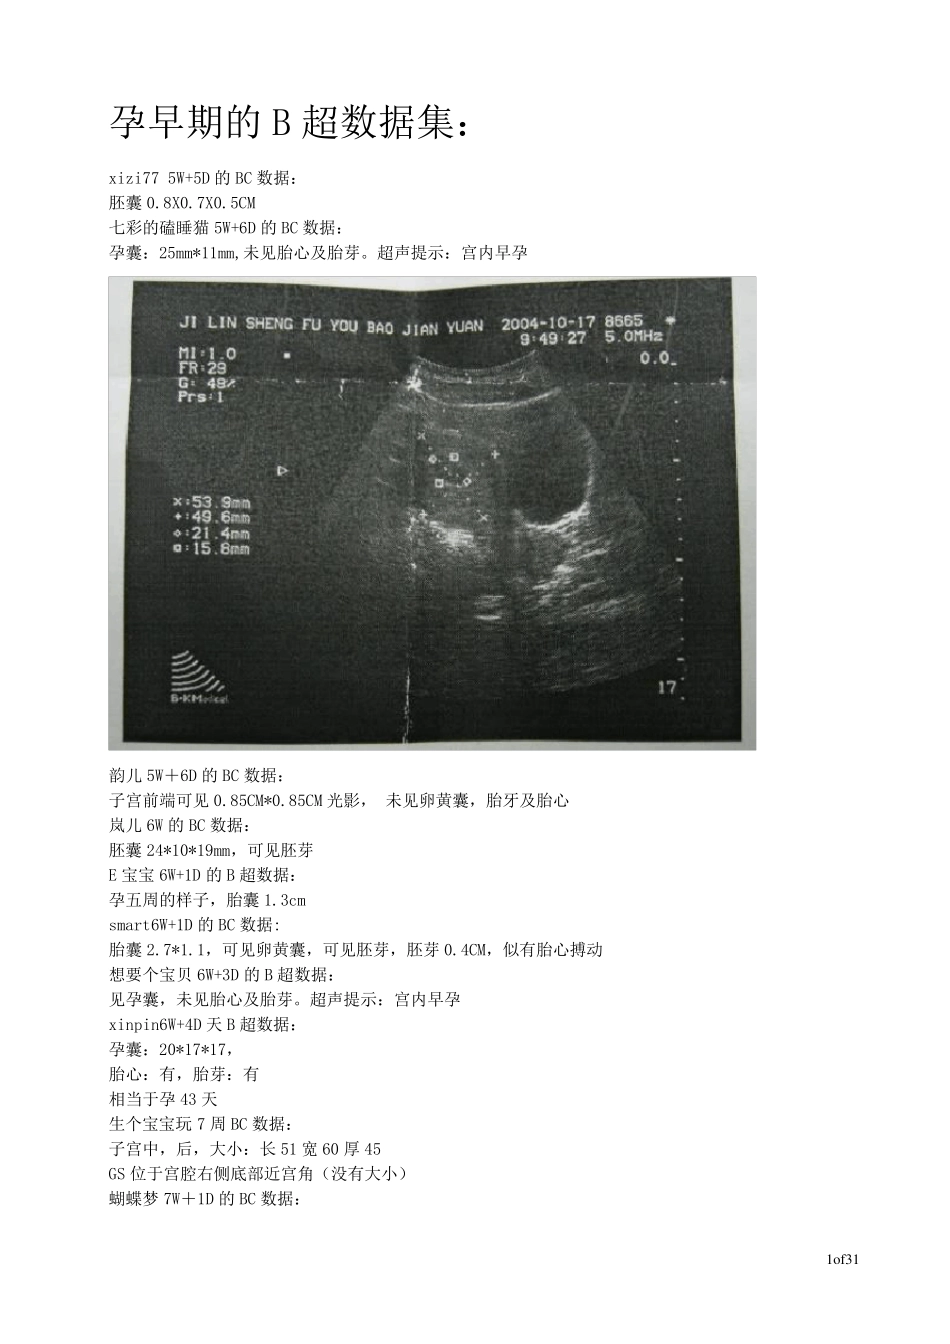

1o f31 孕早期的B 超数据集: xizi77 5W+5D 的BC 数据: 胚囊0.8X0.7X0.5CM 七彩的磕睡猫5W+6D 的BC 数据: 孕囊:25mm*11mm,未见胎心及胎芽。超声提示:宫内早孕 韵儿 5W+6D 的BC 数据: 子宫前端可见0.85CM*0.85CM 光影, 未见卵黄囊,胎牙及胎心 岚儿 6W 的BC 数据: 胚囊24*10*19mm,可见胚芽 E 宝宝 6W+1D 的B 超数据: 孕五周的样子,胎囊1.3cm smart6W+1D 的BC 数据: 胎囊2.7*1.1,可见卵黄囊,可见胚芽,胚芽0.4CM,似有胎心搏动 想要个宝贝 6W+3D 的B 超数据: 见孕囊,未见胎心及胎芽。超声提示:宫内早孕 xinpin6W+4D 天 B 超数据: 孕囊:20*17*17, 胎心:有,胎芽:有 相当于孕43 天 生个宝宝玩 7 周 BC 数据: 子宫中,后,大小:长 51 宽 60 厚 45 GS 位于宫腔右侧底部近宫角(没有大小) 蝴蝶梦 7W+1D 的BC 数据: 2o f31 54 照的b 超,但因为排卵迟了四天,该是50 天,结果:子宫:64x64x50、胚囊:23x17x16、见少许胚芽、两侧附件未见(膀胱尿未充盈)。提示:宫内早孕。准备三个月再照,现在70 天了 柠檬树7W+1D 的B 超图: smart7W+1D 的BC 数据: 胎囊2.9*1.9,胎芽1.2cm,有胎心搏动 jiong_xi7W+3D 的B 超数据: 胎囊4.2X2.2CM,胎芽1.3CM,可见胎心搏动。 笑笑妮7W+4D 的B 超数据: 子宫前位增大,宫内见孕囊,大小35*24 mm,内见胚芽,长10mm,可见原始心管搏动,可见卵黄囊,双侧附件区未见明显异常。 haruka7W+4D 的B 超数据: 增大的子宫腔内可探及一27×30×16mm的妊娠囊,妊娠囊的形态,位置正常,囊内可见胚芽,可见胎心博动,可见卵黄囊回声。 期待天使 7W+5D 的B超数据: 子宫附件:子宫位置 前位,宫体增大 宫内见一孕襄,大小约 34*25*23mm,内可见胚芽及心管博动,双附件无殊。 超声提示:宫内早孕 baier7周多的B 超数据: 子宫前屈位,切面内径74*54*65,形态增大,回声均匀。宫内见一孕囊,囊内见胚芽,见心管博动。双附件未见异常,盆腔未见积液。超声提示,宫内孕,胚胎存活。 这是我 8 周的B 超数据: 子宫增大,宫内见3.8*2.3CM 妊娠囊,囊内可见胎芽,及原始心管博动。 3o f31 七彩的磕睡猫8W+1D 的BC 数据: 孕囊:49mm*25mm,胎芽18mm,胎心(+),超声提示:宫内早孕,胚胎存活 想念笨笨8W+1D 的BC 数据: 超升所见:子宫:前位,宫腔内见一孕囊,大小为43...